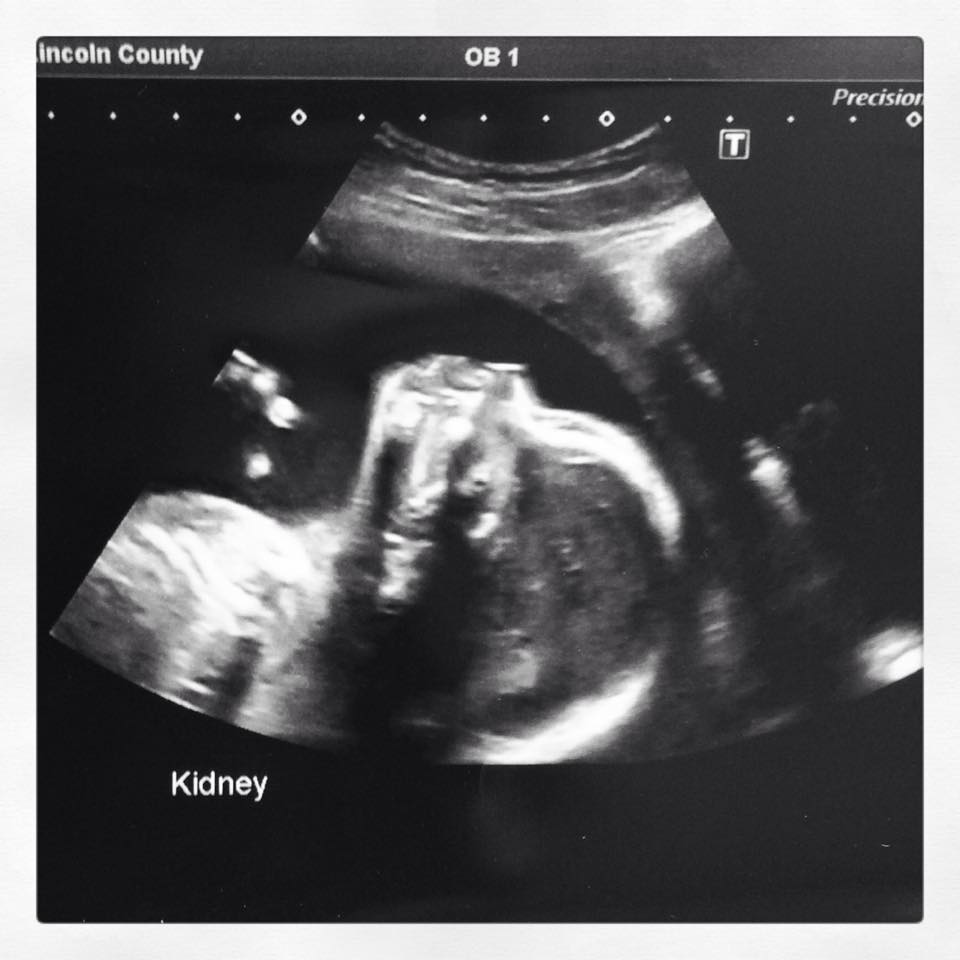

We had our 20 week scan today - 20 weeks 6 days - and didn't find out!!! DH request!!! I'm so curious though - any guesses please?